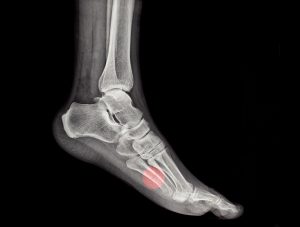

There are two types of foot fractures: stress fractures and general bone fractures. Stress fractures usually occur in the bones of the forefoot extending from the toes to the middle of the foot. Stress fractures are like tiny cracks in the bone surface. They can happen with sudden increases in exercise (such as running or walking for longer distances or times), improper training techniques, or a change in surfaces.

Most other types of fractures extend through the bone, and are called bone fractures. They may be stable, in which there is no shift in bone alignment, or displaced, in which the bone ends no longer line up properly. Bone fractures usually result from trauma, such as dropping a heavy object on your foot, or from a twisting injury. If the fractured bone does not break through the skin, it is called a closed fracture. If the fracture does break through the skin, it is called an open fracture.

Because of the complex structures in the foot, there are some other, more specific types of fractures that can occur. For example, the fifth metatarsal, known as the little or pinky toe, is susceptible to a variety of different fractures. The relationship between the ankle and the foot can be compromised by an ankle-twisting injury, which may tear the tendon that attaches to this bone and pull a small piece of the bone away. A more serious injury in the same area is known as a Jones fracture, which occurs near the base of the bone and disrupts its blood supply. This injury may take longer to heal or require surgery.

Common symptoms for any type of foot fracture includes pain, swelling, and sometimes bruising. Be sure to seek medical attention for any suspected foot fracture.

an x-ray of a human metatarsal bone fracture, diagnosis, broken